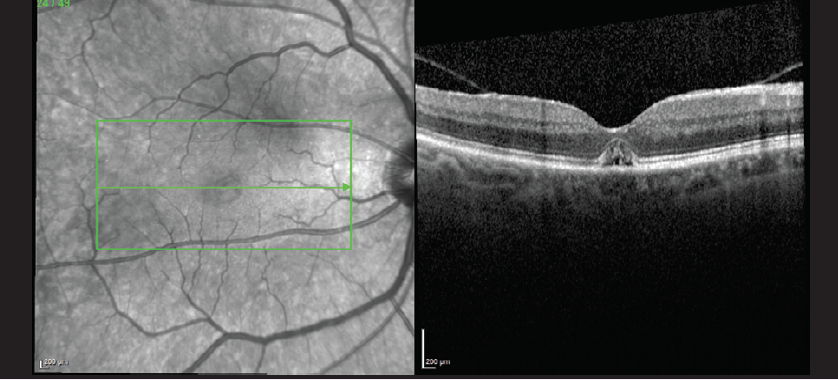

UPDATE ON A CASE FROM A PAST ISSUE

After the January/February issue went to press, Brian C. Joondeph, MD, MPS, informed the editorial staff that the patient profiled in the cover series article “An Elusive Macular Hole Closed by Eye Drops Alone” returned to his office for follow-up. As of February 2020, the patient's VA was 20/30 and further fluid reduction had been demonstrated. To read this case, click the image below.